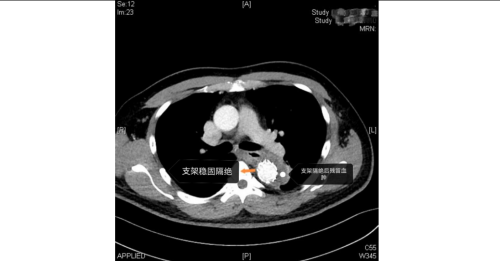

手术室内,患者血压一度飙至惊人的320/150mmHg,循环濒临崩溃!麻醉团队全力稳定循环。在患者下肢几乎无法触摸到脉搏的极端条件下,外周血管介入科主任赵扬程及团队迎难而上,凭借精湛技术,精准置入支架,成功封堵主动脉内膜巨大破口,并精细重建了主动脉弓部受累的重要分支血管,恢复关键血流。这场持续近3小时的手术每一步都高风险且高度紧张,如同在死神面前进行“拆弹”。最终,这颗“血管炸弹”被成功拆除。